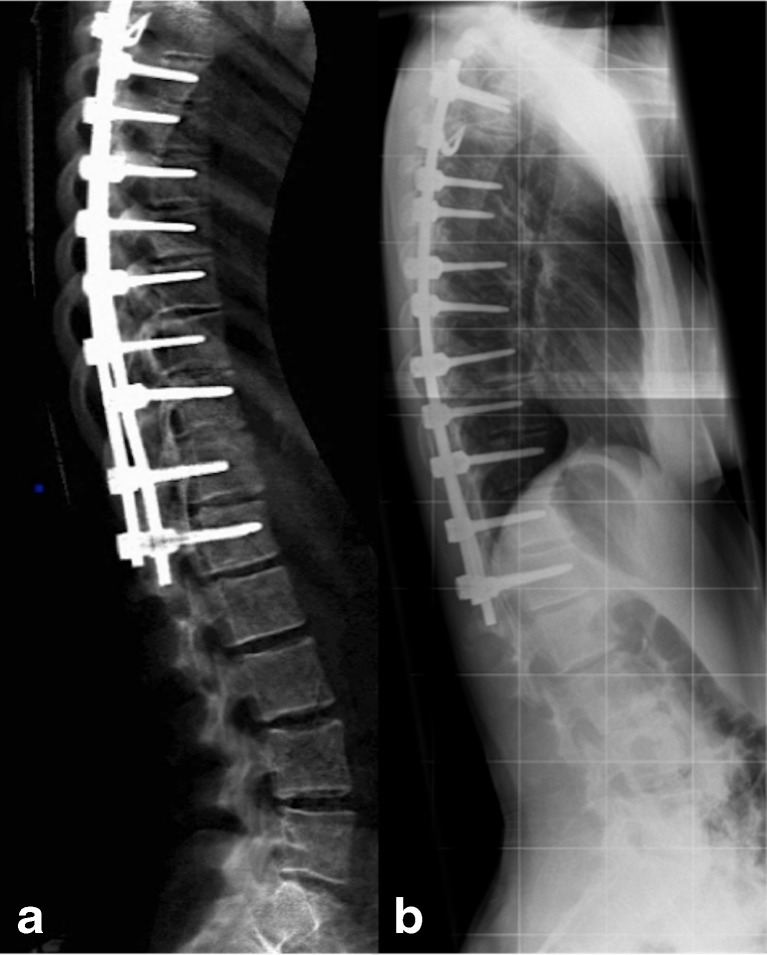

I dati morfometrici ad alta risoluzione stanno diventando la base per la chirurgia spinale personalizzata.

Durante gli interventi di vertebroplastica o cifoplastica (iniezione di cemento osseo per stabilizzare una frattura dolorosa), i chirurghi possono ora indossare visori che sovrappongono il modello morfometrico 3D del paziente alla sua anatomia reale, guidando l’ago con precisione millimetrica sfruttando quindi la realtà aumentata.

Sistemi come ExcelsiusGPS™ utilizzano coordinate morfometriche per posizionare impianti e protesi, riducendo drasticamente il rischio di complicanze neurologiche e vascolari legate a traiettorie errate.